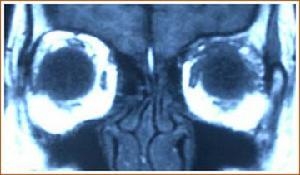

3.MRI 淋巴瘤多位于泪腺,眼睑,也可弥漫侵及眶内软组织,在MRI上TlWI多为中信号,T2WI为高信号,或中高异质信号,增强明显,由于病变呈浸润性增生,可显示包绕眼眶正常结构,甚至充满眼眶。